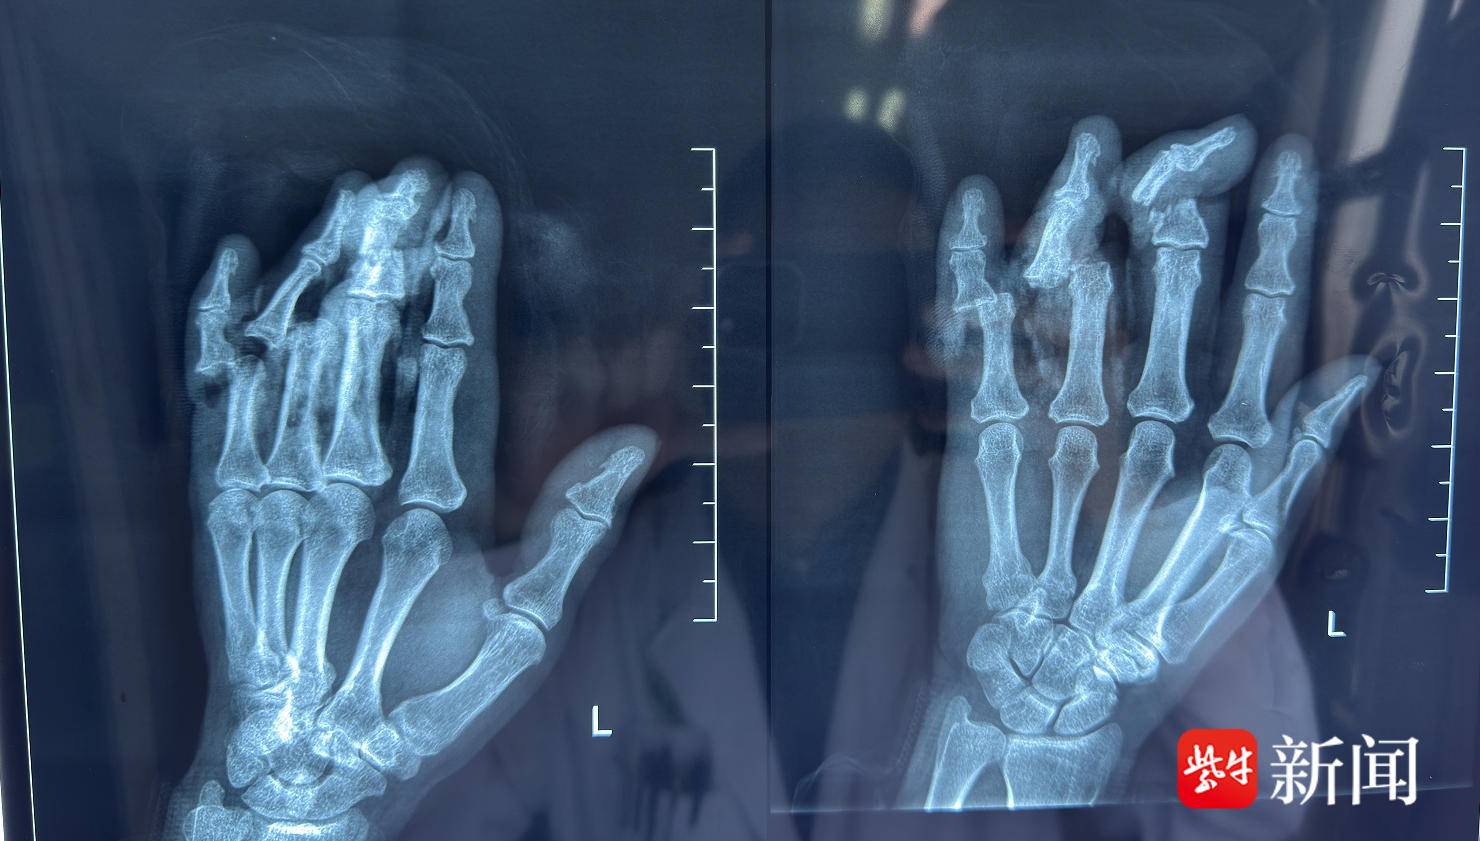

快一分钟就多一分手指接成功的概率。患者转运至中大医院后,医院立即启动救治绿色通道,急诊医护人员第一时间联系烧伤整形科会诊,迅速为患者完善影像学检查。“患者左手3、4、5指完全离断,局部挫伤严重,仅残余部分皮肤及软组织连接。”接诊患者的烧伤整形科王柯医师介绍。检查结果明确显示患者左手中指骨折,左手环指中节骨基底旁见小片状骨性密度影,左手第4、5指近节关节脱位。